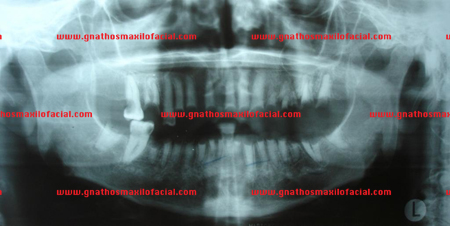

Asimismo, en los casos donde el paciente ha sido sometido a radiación por tratamiento de cáncer, la dentición se ve afectada por caries agresiva que destruye la estructura dental, llevando a restos radiculares múltiples. Las siguientes imágenes son un ejemplo de ello.

![]() |

| Radiografías panorámicas antes y después de extracciones múltiples con regularización de proceso alveolar

|